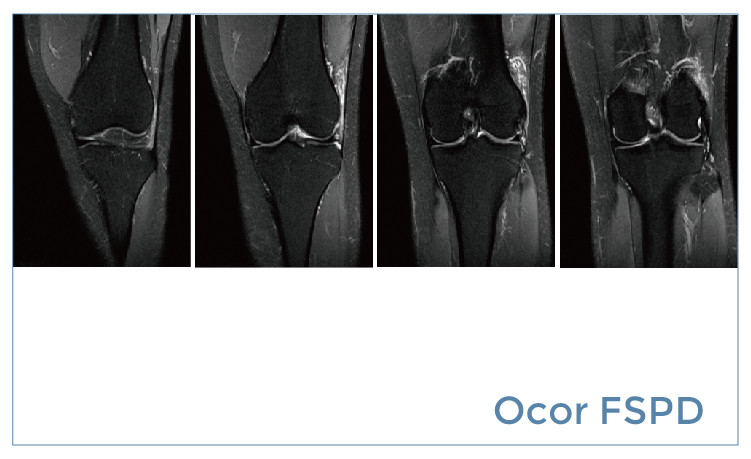

【朗润影像档案】20190510磁共振影像病例结果讨论